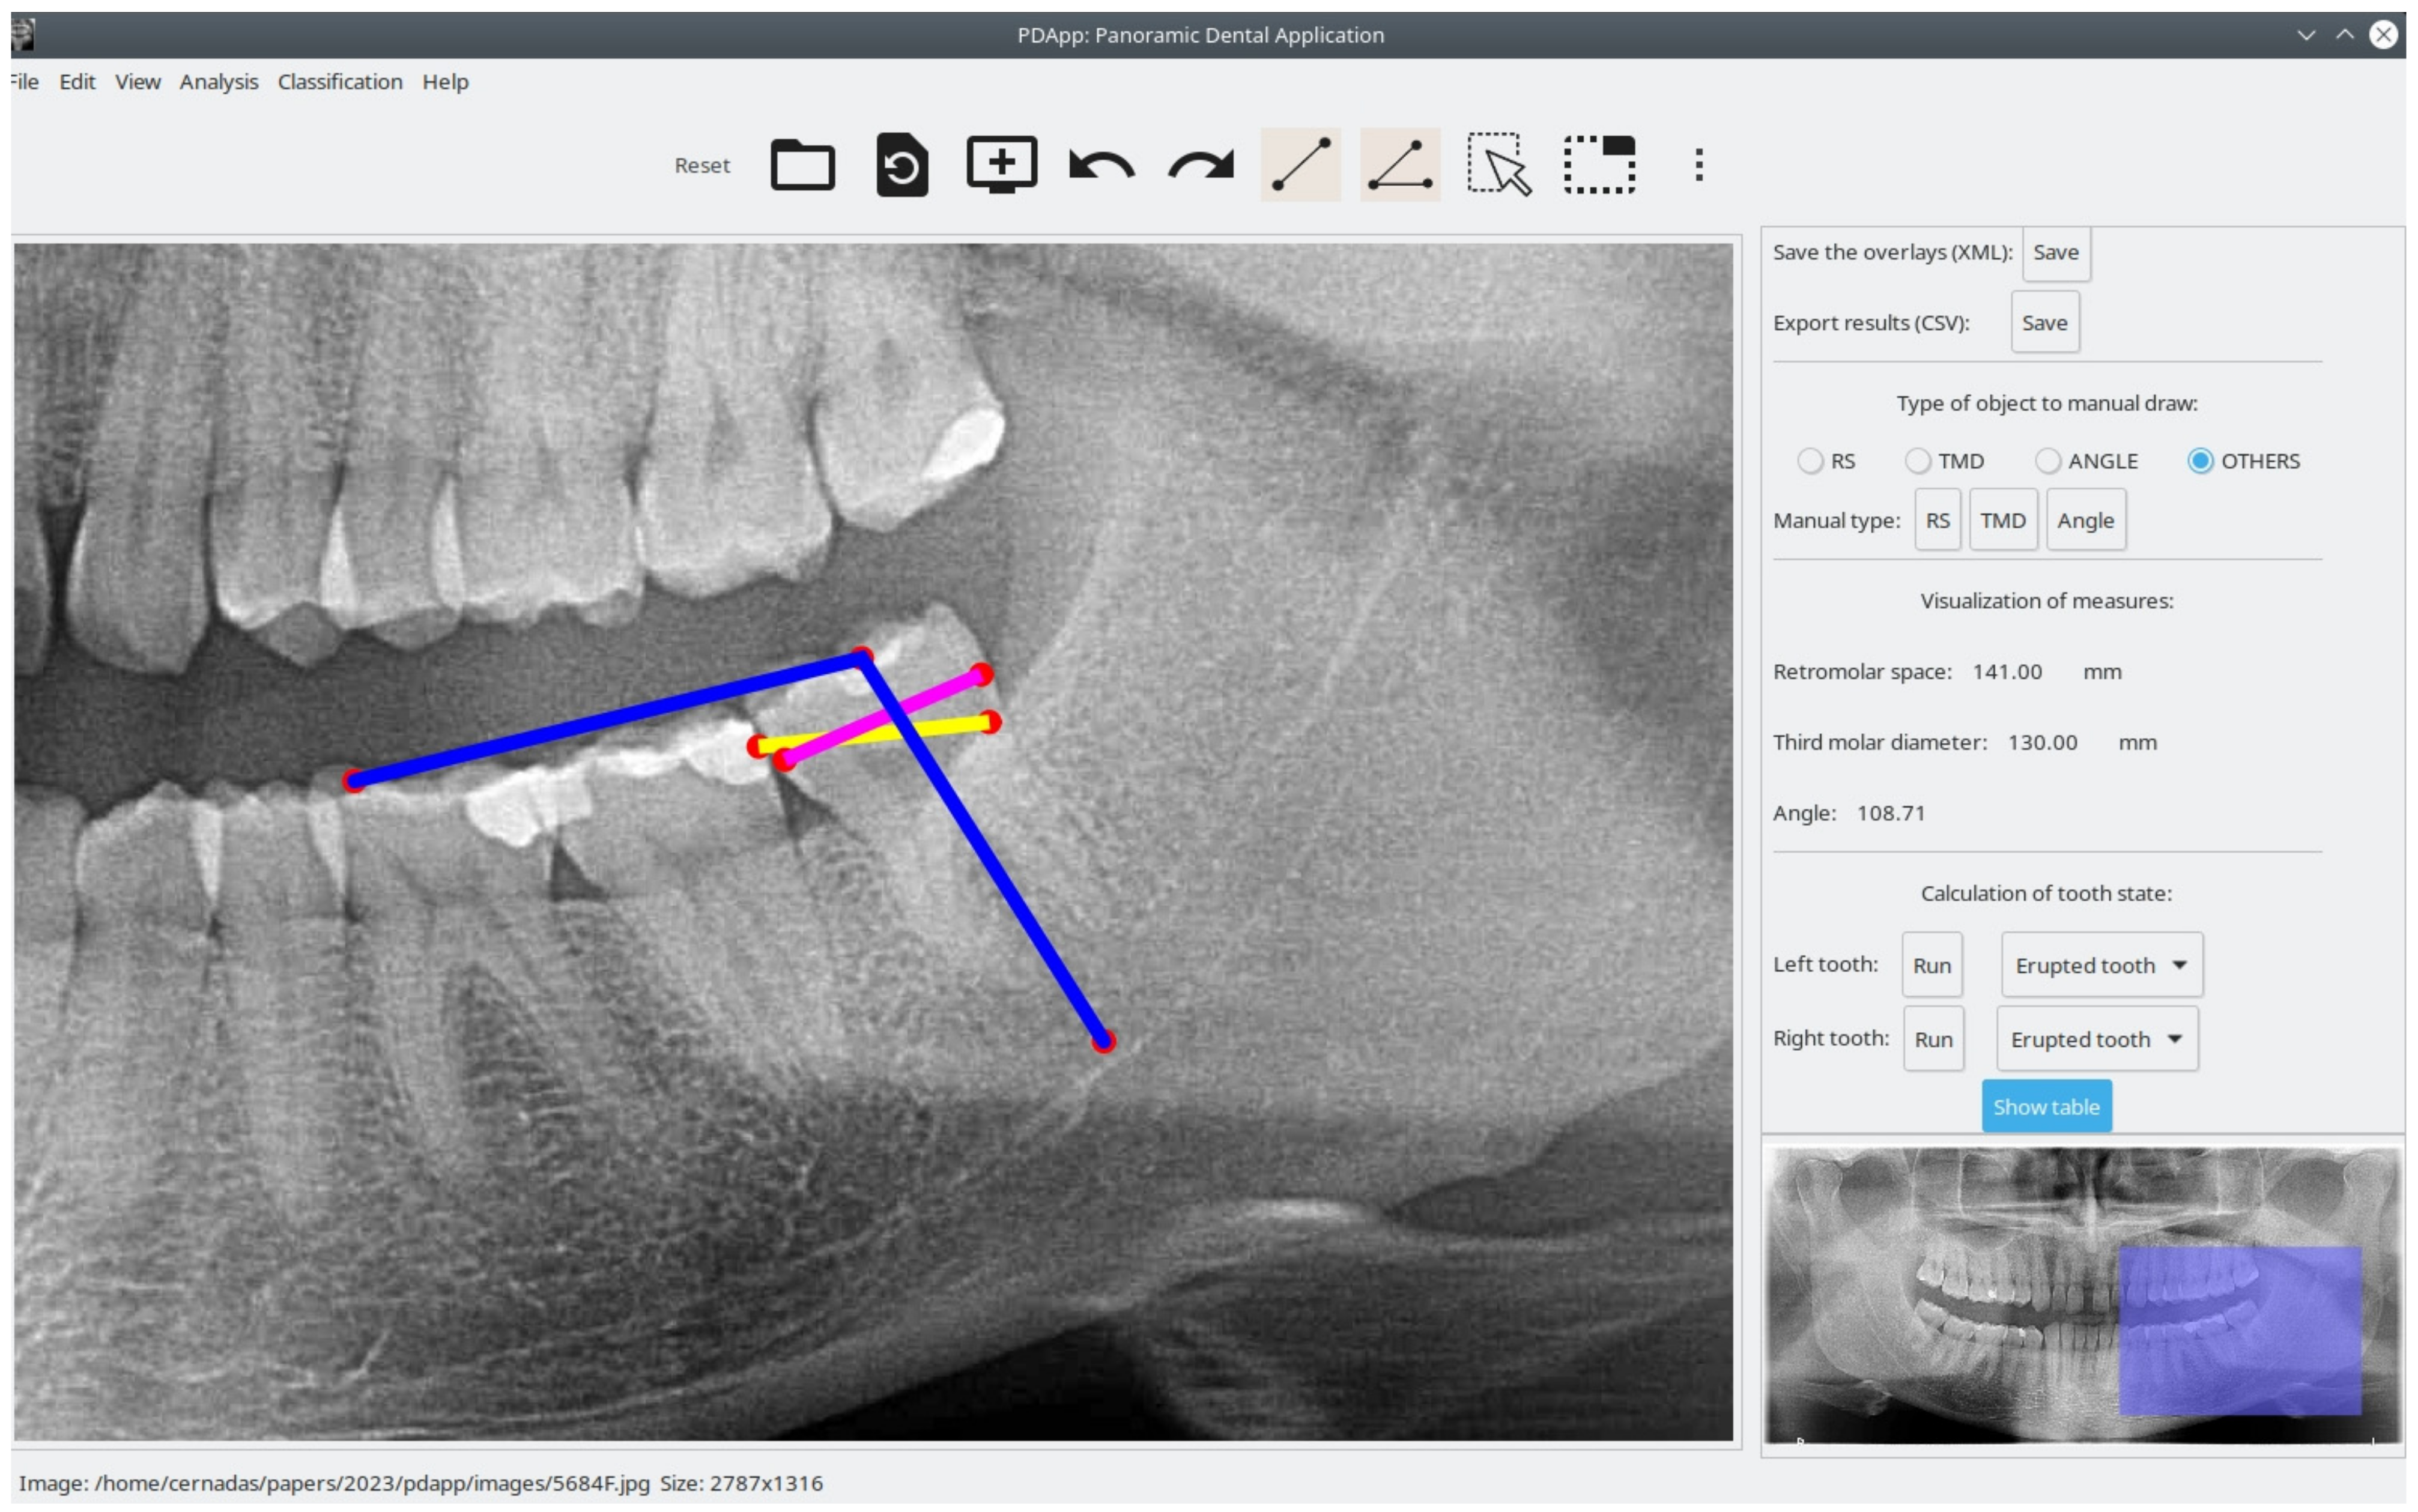

- Provide a friendly GUI to interactively work with radiological images and draw lines and angles for analysis.

- Measure lines and angles in the images.

- Manually draw the retromolar space, the third molar diameter, and the angle for each third molar.

- Automatically measure the distances and angles.

- Automatically classify the third molars.